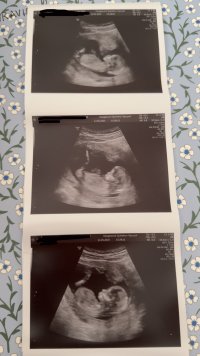

Man ser lårbenet på alle tre, og da kan man ikke se nub dessverreKan man se noe på disse?

Det ene er uke 12+0 og de to siste er 12+5

SkjønnerMan ser lårbenet på alle tre, og da kan man ikke se nub dessverre